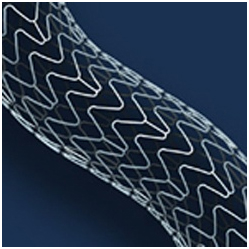

Вместе с тем, проведение селективной коронарной ангиографии с последующей ангиопластикой и установкой стентов, выделяющих лекарственное покрытие, требовало бы длительного приема двойной антиагрегантной терапии (плавикс, ацетилсалициловая кислота), что увеличит риск геморрагических осложнений в условиях предстоящей урологической операции и в послеоперационном периоде.

2. Отягощающим фактором является ИБС со стенозированием коронарных артерий, обнаруженным по данным МСКТ коронарных артерий. С учетом того, что при проведении Холтеровского мониторирования ЭКГ имеется стресс-индуцированная ишемия миокарда, то в ближайшее время показано проведение селективной коронарной ангиографии. При необходимости будут установлены стенты без лекарственного покрытия с последующей антикоагулянтной терапией гепарином и отменой данного препарата в минимальные сроки перед очередным оперативным вмешательством. Выбор данного вида стентов обусловлен возможностью проведения менее интенсивного режима антиагрегантной терапии в условиях предстоящей операции нефрэктомии, а также в послеоперационном периоде.

18.08.2011 интервенционным кардиохирургом в область стеноза проксимальной трети передней межжелудочковой артерии проведен баллонный катетер со стентом «Мульти-линк 8» размерами 3×12 мм, произведена имплантация.

В дистальную часть правой коронарной артерии проведен проводник 0,014″. В область стеноза проведен баллонный катетер со стентом «Мульти-линк 8» размерами 3×12 мм, произведена имплантация.

Ишемическая болезнь сердца. Стенокардия напряжения II функционального класса. Атеросклероз коронарных артерий. Ангиопластика и стентирование передней нисходящей артерии стентом без лекарственного покрытия «Мульти-линк 8» размерами 3×12 мм. Ангиопластика и стентирование правой коронарной артерии стентом без лекарственного покрытия «Мульти-линк 8» размерами 3×12 мм от 18.08.2011.

В тех случаях, когда развитие атеросклероза достигает того этапа, при котором появляются клинические симптомы того или иного заболевания, связанного с атеросклерозом, начинают лечить само это заболевание, или точнее будет сказать, атеросклеротическое поражение того или иного органа: сердца, мозга, почек, нижних конечностей. Причем нередко это лечение может быть хирургическим. [11] Обычно такое лечение состоит в хирургических воздействиях, локально восстанавливающих проходимость пораженных атеросклерозом артерий. Например, при поражении сосудов сердца это может быть малотравматичная операция по установке в месте сужения специального внутрисосудистого каркаса — стента, которая проводится через прокол в сосуде, а может быть и «большая» операция коронарного шунтирования со вскрытием грудной клетки и наложением путей обходного кровотока в сердце — шунтов. При этом атеросклероз как системное заболевание остается, и хирургическое лечение никоим образом не отменяет необходимость лечить его — прежде всего, корректируя факторы риска, среди которых крайне важным является нарушенное соотношение фракций липопротеинов, содержащих холестерин.